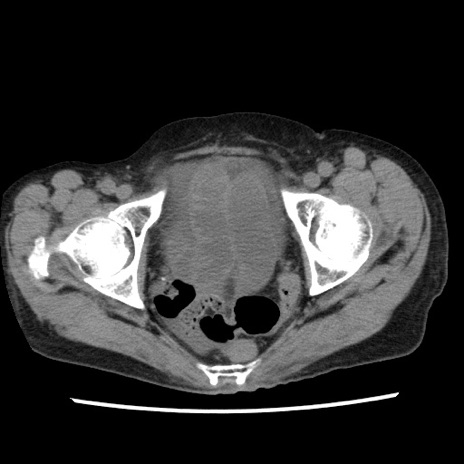

症例1(横断像)

【症例】80歳代女性

【主訴】腹痛

【現病歴】8時間前から腹痛あり来院。

【既往歴】糖尿病、脂質異常症、子宮体癌にて子宮全摘術

【身体所見】意識清明・会話良好だが腹痛で苦悶様、全腹部にわたって反跳痛と圧痛あり

【データ】WBC 13600、CRP 0.14、LDH 224、CK 90